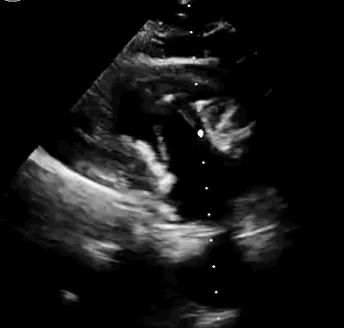

上海中山醫(yī)院葛均波院士、錢菊英院長、周達(dá)新教授、潘文志教授、潘翠珍教授、李偉教授共同完成此次臨床前研究。術(shù)后葛均波院士對Lux-Valve Plus的器械操作性能給予了高度評價(jià),DSA和超聲影像也顯示出在本次研究中Lux-Valve Plus的安全性和有效性俱佳。

本次臨床前研究經(jīng)右側(cè)頸靜脈置入LuX-Valve Plus輸送系統(tǒng)可調(diào)彎鞘管,在DSA及超聲引導(dǎo)下將人工三尖瓣瓣膜植入到原有三尖瓣位置,利用獨(dú)特的錨定技術(shù)將人工瓣膜支架可靠固定在預(yù)定的位置。